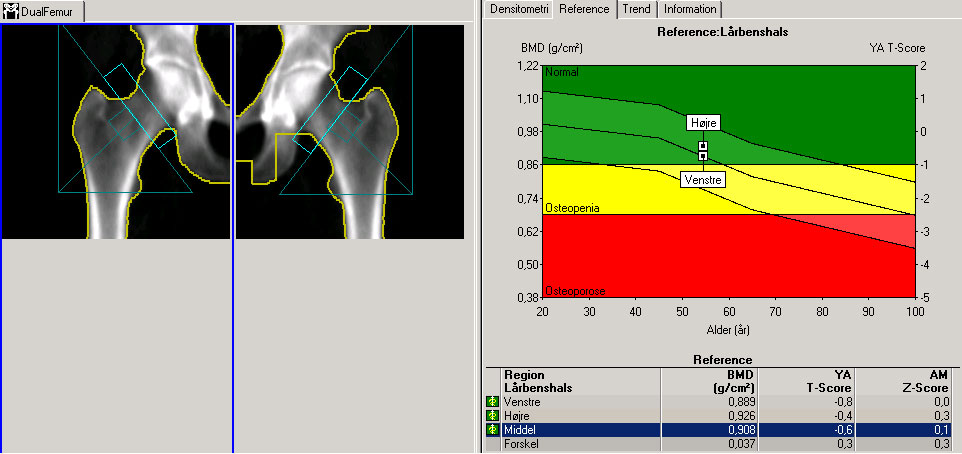

Hofter, DXA-skanning, normalbillede

Skanningsbilledet viser resultater fra en DXA-skanning af normale hofter, det vil sige uden knogleskørhed (osteoporose).

Kilde til skanningsbillede: Afdeling for Nuklearmedicin, Herlev Hospital